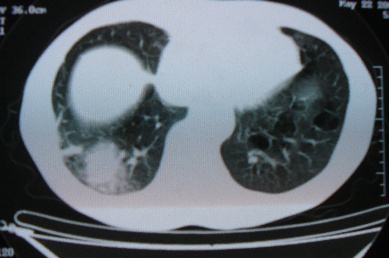

ct10716,男,59岁。发热咳嗽一天,咯血一次入院。

病灶中心有低密度,气体,病灶周围炎性浸润可能为肺脓肿,量体温、查个痰就是了,但肺脓肿一般都多少会有点兄水的。左肺下局部密度减低,小叶中心肺气肿。

病灶边缘较模糊,中心见低密度影及少量气影,宽基与胸膜相连,周围见炎性浸润,考虑右下肺脓肿。

病灶边缘较模糊,中心见低密度影及少量气影,宽基与胸膜相连,周围见炎性浸润,考虑右下肺脓肿。建议治疗后复查。

右下肺病灶,边缘模糊,中心见低密度坏死区及气体影,结合病史较短,以发热为主,考虑右下肺脓肿,建议抗炎治疗后复查。